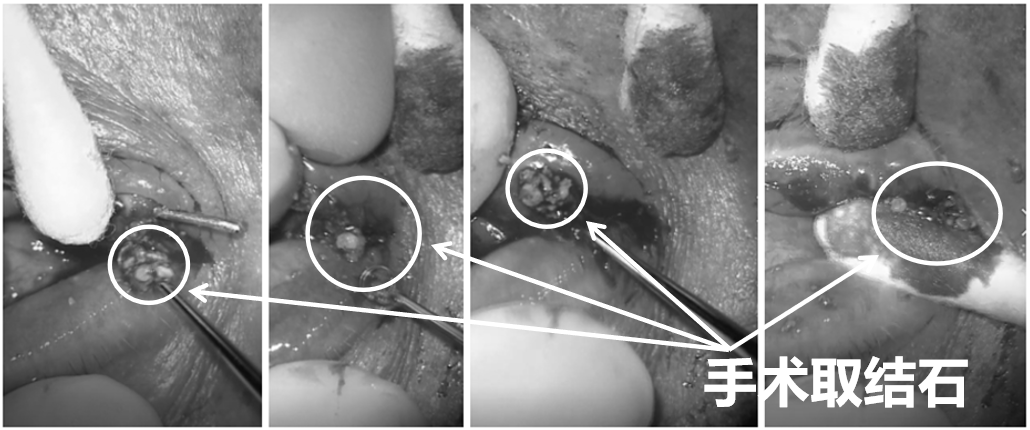

4月22日,在无影灯的照射下,一根9号泪道探针连带一条直径为1mm的人工泪管,自下泪点探进患者泪小管,随后,徐主任切开下泪小管,用挖勺,小心地开始清理其中的结石。

“我们从没见过泪小管甚至鼻泪管中存在这么多的结石,实在太多了。”徐主任术后回忆道,“我们用挖勺大概清理了10分钟才处理干净。”

▲术中影像:取结石(已调色)